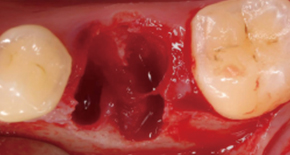

2. Bone graft